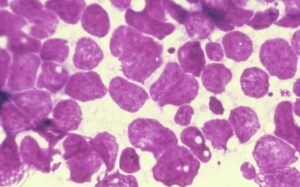

Рак легкого — это собирательный термин, обозначающий образование и рост злокачественных опухолей, различающихся по структуре, происхождению и другим характеристикам. Обычно он возникает из эпителия слизистой оболочки или желез бронхиальной стенки или альвеол. Немелкоклеточный рак легкого встречается относительно реже, чем другие формы заболевания. Как это диагностируется и лечится? Причины крупноклеточной опухоли У большинства пациентов, страдающих данной …

Химиотерапия — одно из методов лечения рака легких. Однако это осложняется токсическим действием препаратов. Это пугает пациентов и часто вынуждает их отказаться от лечения. Между тем, большинство побочных эффектов обратимы. Чтобы лечение прошло без осложнений, необходимо знать, как себя вести во время и после процедур. Виды и принцип действия препаратов Химиотерапия — это метод консервативного …